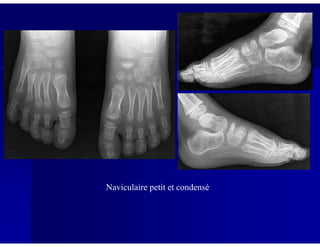

Naviculaire petit et condensé

Köhler-Mouchet

Clichés réalisés à 7 mois d’intervalle chez un enfant qui se plaint de douleurs de

l’avant-pied: os naviculaire devenu petit et condensé alors qu’il était préalablement

normal.

Patient asymptomatique : aspect petit et condensé du naviculaire (variante

anatomique)